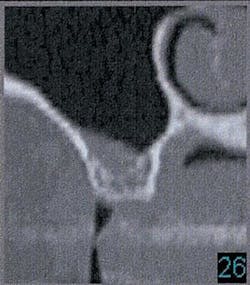

Figure 2a - CT scan showing large bone defect

Figure 12 - CT scan demonstrating insufficient bone for implants (SimPlant software)